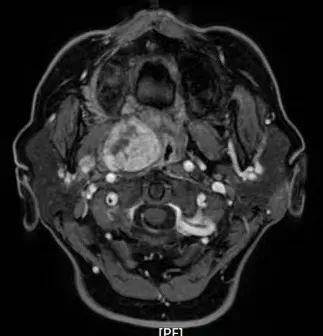

病例1:患者男,56岁,因反复鼻出血入院,入院CT、MRI示肿瘤侵犯右侧翼腭窝、颞下窝、翼突根及翼内外板。入院诊断:侧颅底恶性肿瘤。肿瘤范围大,难度大,风险高。

科室副主任刘永亮立即组织颅底肿瘤团队进行病例讨论,决定全麻经鼻内镜联合唇龈沟入路切除肿瘤,术中肿瘤完全切除。术后病理:(右侧鼻腔)纤维上皮瘤恶变为鳞状上皮原位癌。

CT、MRI示肿瘤侵犯右侧翼腭窝、颞下窝、翼突根及翼内外板